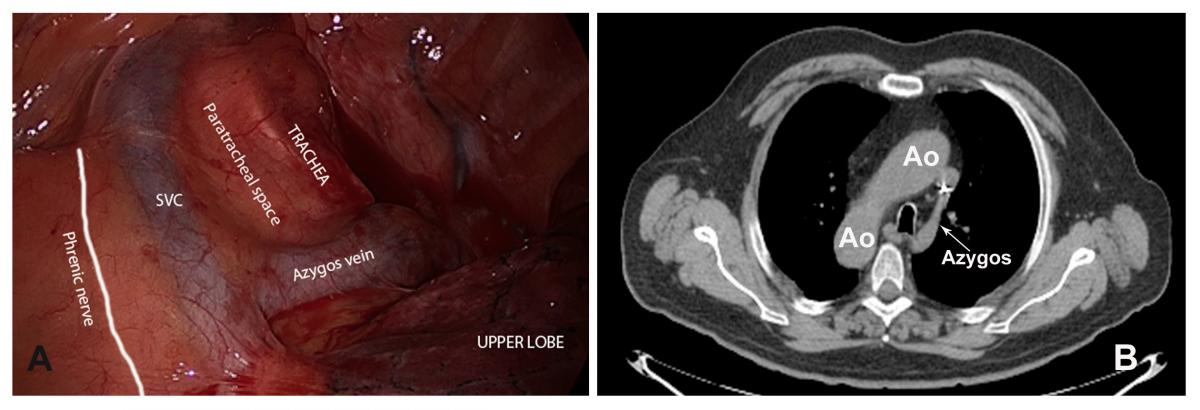

Surgical technique:The patient was placed in a right lateral decubitus position. An uniportal video-assisted thoracoscopic approach through a single 4 cm incision was made in the left 5th intercostal space with no rib spreading. The left lung composed of three lobes and vascular and bronchial anatomy was exactly as a normal right side lung. Azygos vein, superior vena cava, and paratracheal space were mirror images of normal condition (Fig. 1A,B).